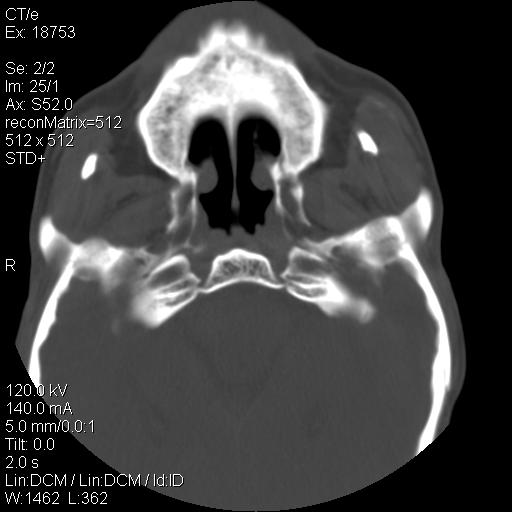

标题: CT21693:男 58岁 右侧咽部疼她2天余 PE:右侧扁桃体肿大 压痛 [打印本页]

标题: CT21693:男 58岁 右侧咽部疼她2天余 PE:右侧扁桃体肿大 压痛

右化脓性扁桃体炎症伴咽后壁脓肿形成.